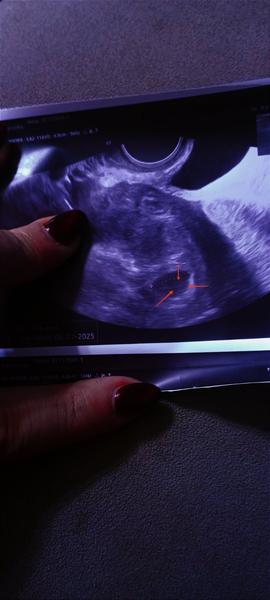

Holky, tak už tam je 🙂 plod 3 mm, srdeční akce pomalinku naskakuje 🥰❤️ 6+1 TT, ale podle utz o malinko menší. Ovu byla až 17 DC, to vím.

Po týdnu tedy ťuká srdíčko ❤️🥰